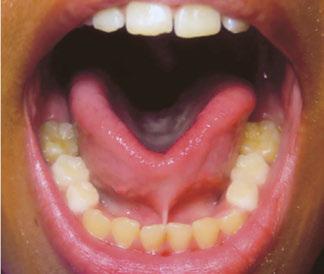

At the postoperative consultation with the mother, we told her the tooth’s complete root formation might prevent its eruption. Orthodontic extrusion of the incisor was ruled out due to his behavior. A conservative approach with observation only was elected as treatment modality. This patient returned for follow-up appointments at ages 10, 11, 12, and 13. During all these visits, the maxillary right permanent central incisor had not erupted. At age 14, due to recurrent dental caries, the patient was taken to the local children’s hospital for dental rehabilitation again. During this second hospitalization, we noticed that the right maxillary central incisor was partially erupted into the oral cavity (Figure 4).

Figure 4: Photograph of area at 14 years old during second rehabilitation under general anesthesia